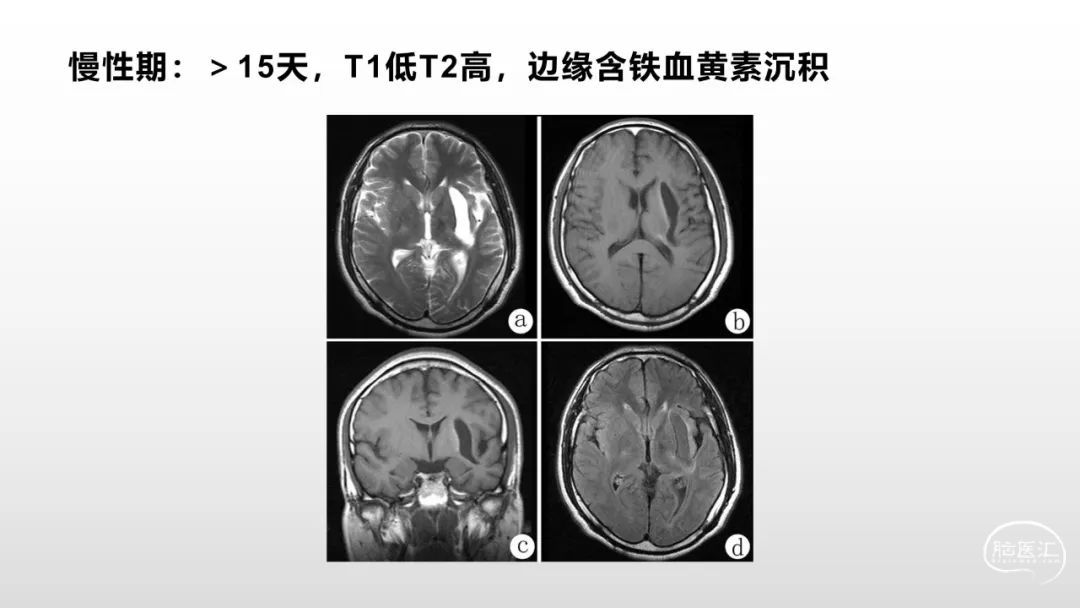

颅脑影像诊断基础知识讲座:《脑血管病》之出血、血管畸形、动脉炎及神经卡压